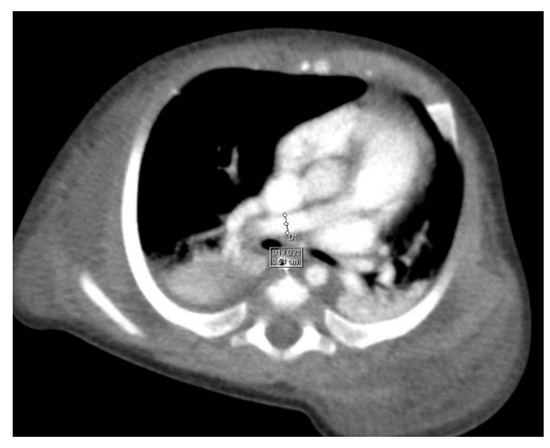

Through thoracic CT, we found SVC with a diameter of 15 mm (Figure 1), a venous collector with a 12 mm in diameter connected to the SVC and identified at the level of a plane passing through the middle of the left superior pulmonary lobe (Figure 2). The venous structure continues superiorly with the left brachiocephalic venous trunk, which was dilated up to 12 mm (Figure 3) and inferiorly with a left pulmonary vein. The pulmonary trunk appeared shorter, with a diameter of 6 mm, right pulmonary artery = 5.4 mm and left pulmonary artery = 5.6 mm (Figure 4 and Figure 5). We have identified traits of pulmonary consolidation (Figure 6).

Figure 4.

Right pulmonary artery.

Figure 5.

Left pulmonary artery.